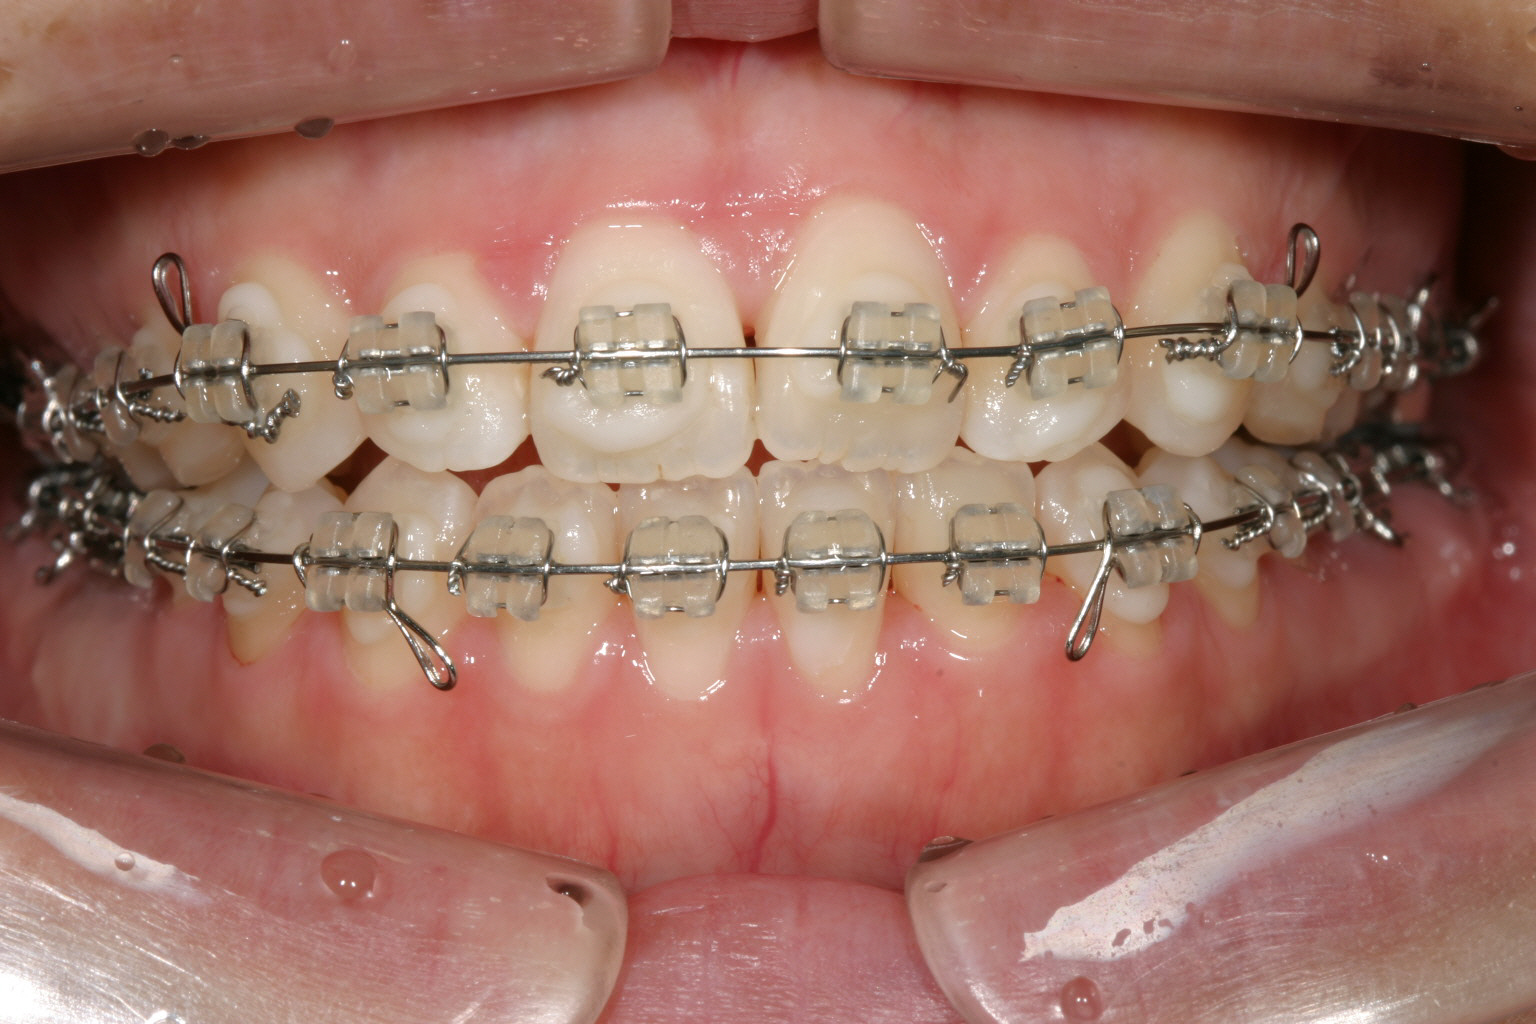

上顎の犬歯と犬歯の幅が狭い為前歯に乱れが有ります。

下顎も上顎と同じく犬歯間幅径が狭く叢生になってます。

治療開始から半年後です。 犬歯間も広がり綺麗に並んできました。

下顎も半年経つとかなり綺麗に並んでいます。

前歯部の開咬も殆どふさがってきています。 正中もピッタリです。 少し受け口傾向の為エラスティックを利用しました。 その為下顎前歯の犬歯のところに下向きの角が見受けられます。